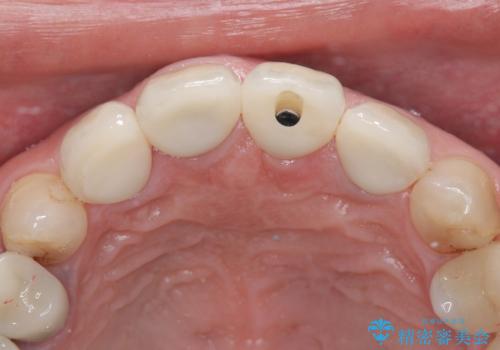

- 治療計画

- 患者様は前歯の審美的な改善を希望されて来院されました。診査の結果、左上1の歯は過去の根管治療により歯根が破折していることが判明し、保存が難しい状態でした。そのため、**長期的な予後を考慮し、抜歯と同時にインプラントを埋入する「抜歯即時インプラント」**を計画。また、隣接する左上2の歯には感染が見られたため、歯根端切除術を同時に行い、感染の除去と治癒を促しました。右上1・2については、セラミッククラウンによる審美修復を行う方針としました。

左上1は抜歯と同時にインプラントを埋入し、骨や歯ぐきの形態を維持しながら治療を進めました。左上2は歯根端切除術により感染部位を除去し、保存治療を実施。右上1・2も含めた前歯4本をセラミッククラウンで修復し、自然な色調と形態を再現しました。治療後は、噛み合わせの安定とともに、美しく自然な前歯を回復することができました。患者様からも「見た目がとても自然で、自信を持って笑えるようになった」と喜びの声をいただきました。